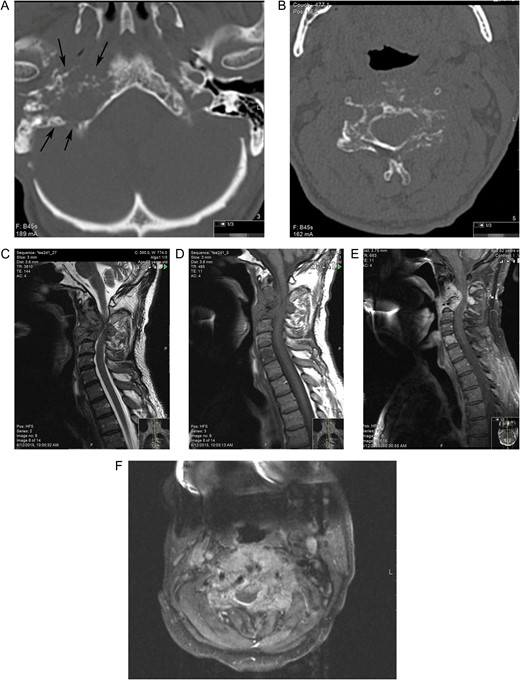

A 52-year-old man presented to our hospital with increasing neck pain and upper extremity weakness. The patient had a history of a right jugular paraganglioma which had been discovered by chance and he had been treated 3 years earlier with intra-arterial embolization. The patient had been found to be disease-free at follow-ups. On computed tomography (CT), a permeative destructive lesion in the right petrous bone arising from the upper portion of the jugular bulb and extending anteriorly to the carotid canal was depicted (Fig. 1A). CT scan and magnetic resonance imaging (MRI) of the patient’s cervical spine showed a destructive mass lesion involving the C2 and C3 vertebral bodies with severe canal stenosis and spinal cord compression. A mottled osteolytic lesion with destruction of C2 and C3 vertebral bodies and involvement of posterior elements was observed (Fig. 1B). MRI showed a hypointense expansile lesion involving the C2 and C3 vertebral bodies with extension into the epidural space compressing the spinal cord. The lesion enhanced homogeneously on post-contrast T1-weighted MR (Fig. 1C–F). Laboratory tests were normal and did not indicate elevated serum normetanephrine/norepinephrine. The patient underwent decompressive surgery with an uncomplicated postoperative course. Histopathological examination revealed an infiltrating neoplasm with tumor cells arranged in solid nests with increased number of mitoses. Tumor cells were positive for chromogranin A. The histologic and immunohistochemical assays were compatible with paraganglioma (Fig. 2). Following his discharge, the patient underwent an outpatient external beam radiation. No family history of paraganglioma was reported.

(A) CT shows a destructive lesion in right petrous bone arising at the level of jugular bulb extending anteriorly to the carotid canal (arrow) (B) CT at the level of C3 reveals mottled osteolytic lesion with destruction of the vertebral body and involvement of posterior elements. MRI demonstrates the lesion to be hypointense on sagittal T1-weighted image (C) isointense on T2-weighted (D) and with avid enhancement on post-contrast sagittal (E) and axial (F) TI fat-sat images and epidural extension of the tumor with spinal cord compression. Note avid enhancement of the metastatic lesion of C5 vertebrae body as well.